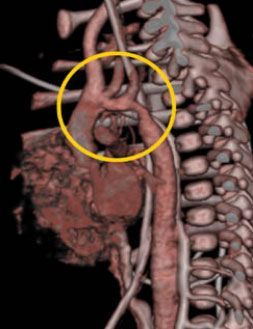

При выявлении или подозрении на аномалии развития аорты и ее ветвей, последствия сифилитического аортита, атеросклеротическом поражении аорты с развитием аневризмы - это далеко весь перечень заболеваний, требующих проведения 64 МСКТ. Также показана возможность визуализации диссекции аневризмы аорты любой локализации [2,3,52].

Интересен клинический случай, описанный Leschka S. с соавт. (2005)[66] - при проведении эндоваскулярной коррекции по поводу коарктации аорты, у больного появились боли в области спины, экстренно выполненная 64 МСКТ позволила диагностировать острую диссекцию аорты, после чего пациенту выполнена открытая аортопластика.

Возможность высокоточной анатомо-топической диагностики, достоверность, скорость получаемой информации определяет необходимость в направлении больных с такой патологией на МСКТ.

![]() |

| Рис.9. МСКТ у пациента с коарктацией аорты (А,В) (стрелка). Аортография (С,D). Контроль за эффективностью эндоскопического лечения, последующее наблюдение(E,F). |

Также МСКТ используется для контроля после хирургического лечения коарктации аорты (рис №9)[55].